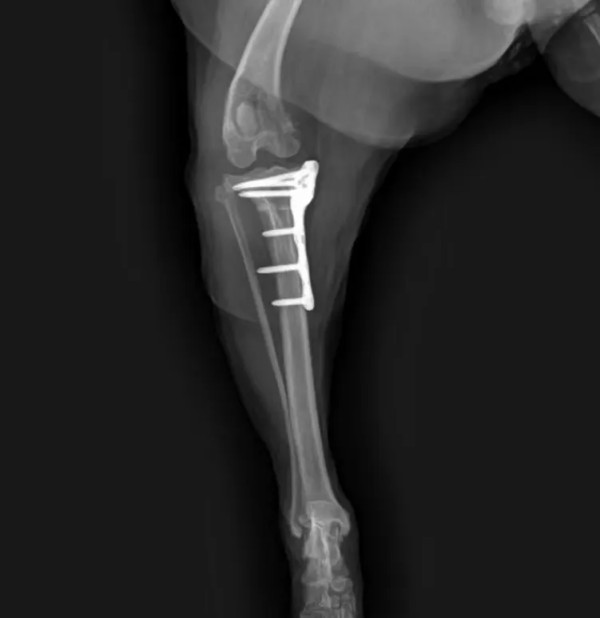

选用2.0型号宠多助TPLO-L骨板,术前TPA=30角°,应用10mm锯片,移动距离4.5mm

手术顺利完成,望早日康复!

术后X光片